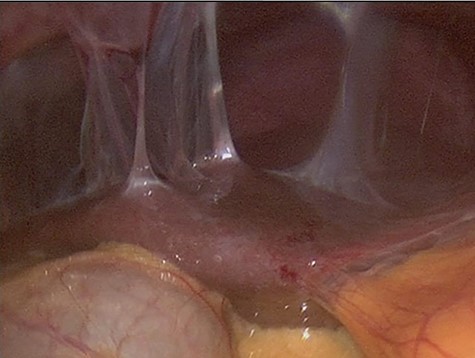

The decision to conduct a colonoscopy was undertaken to exclude inflammatory bowel disease and lower gastrointestinal (GIT) pathology. Colonoscopy revealed several adhesions throughout the pelvic organs (Fig. 1) and a biopsy revealed blunting of villi with subsequent crypt hyperplasia with no crypt abscesses, fistulas or granulomas (Fig. 2). There was a high clinical suspicion of celiac disease and laboratory confirmation was ordered. Lab results: positive immunoglobulin A (IgA) anti-tissue glutaminase 4.6 and immunoglobulin G (IgG) antideamidated gliadin peptide antibodies, IgA tTG 167 U/ml. Laparoscopy was performed as well to exclude any hidden etiologies including gynecological disorders that can lead to the adhesions but was not able to identify the cause.

Colonoscopy revealed several adhesions throughout the pelvic organs.